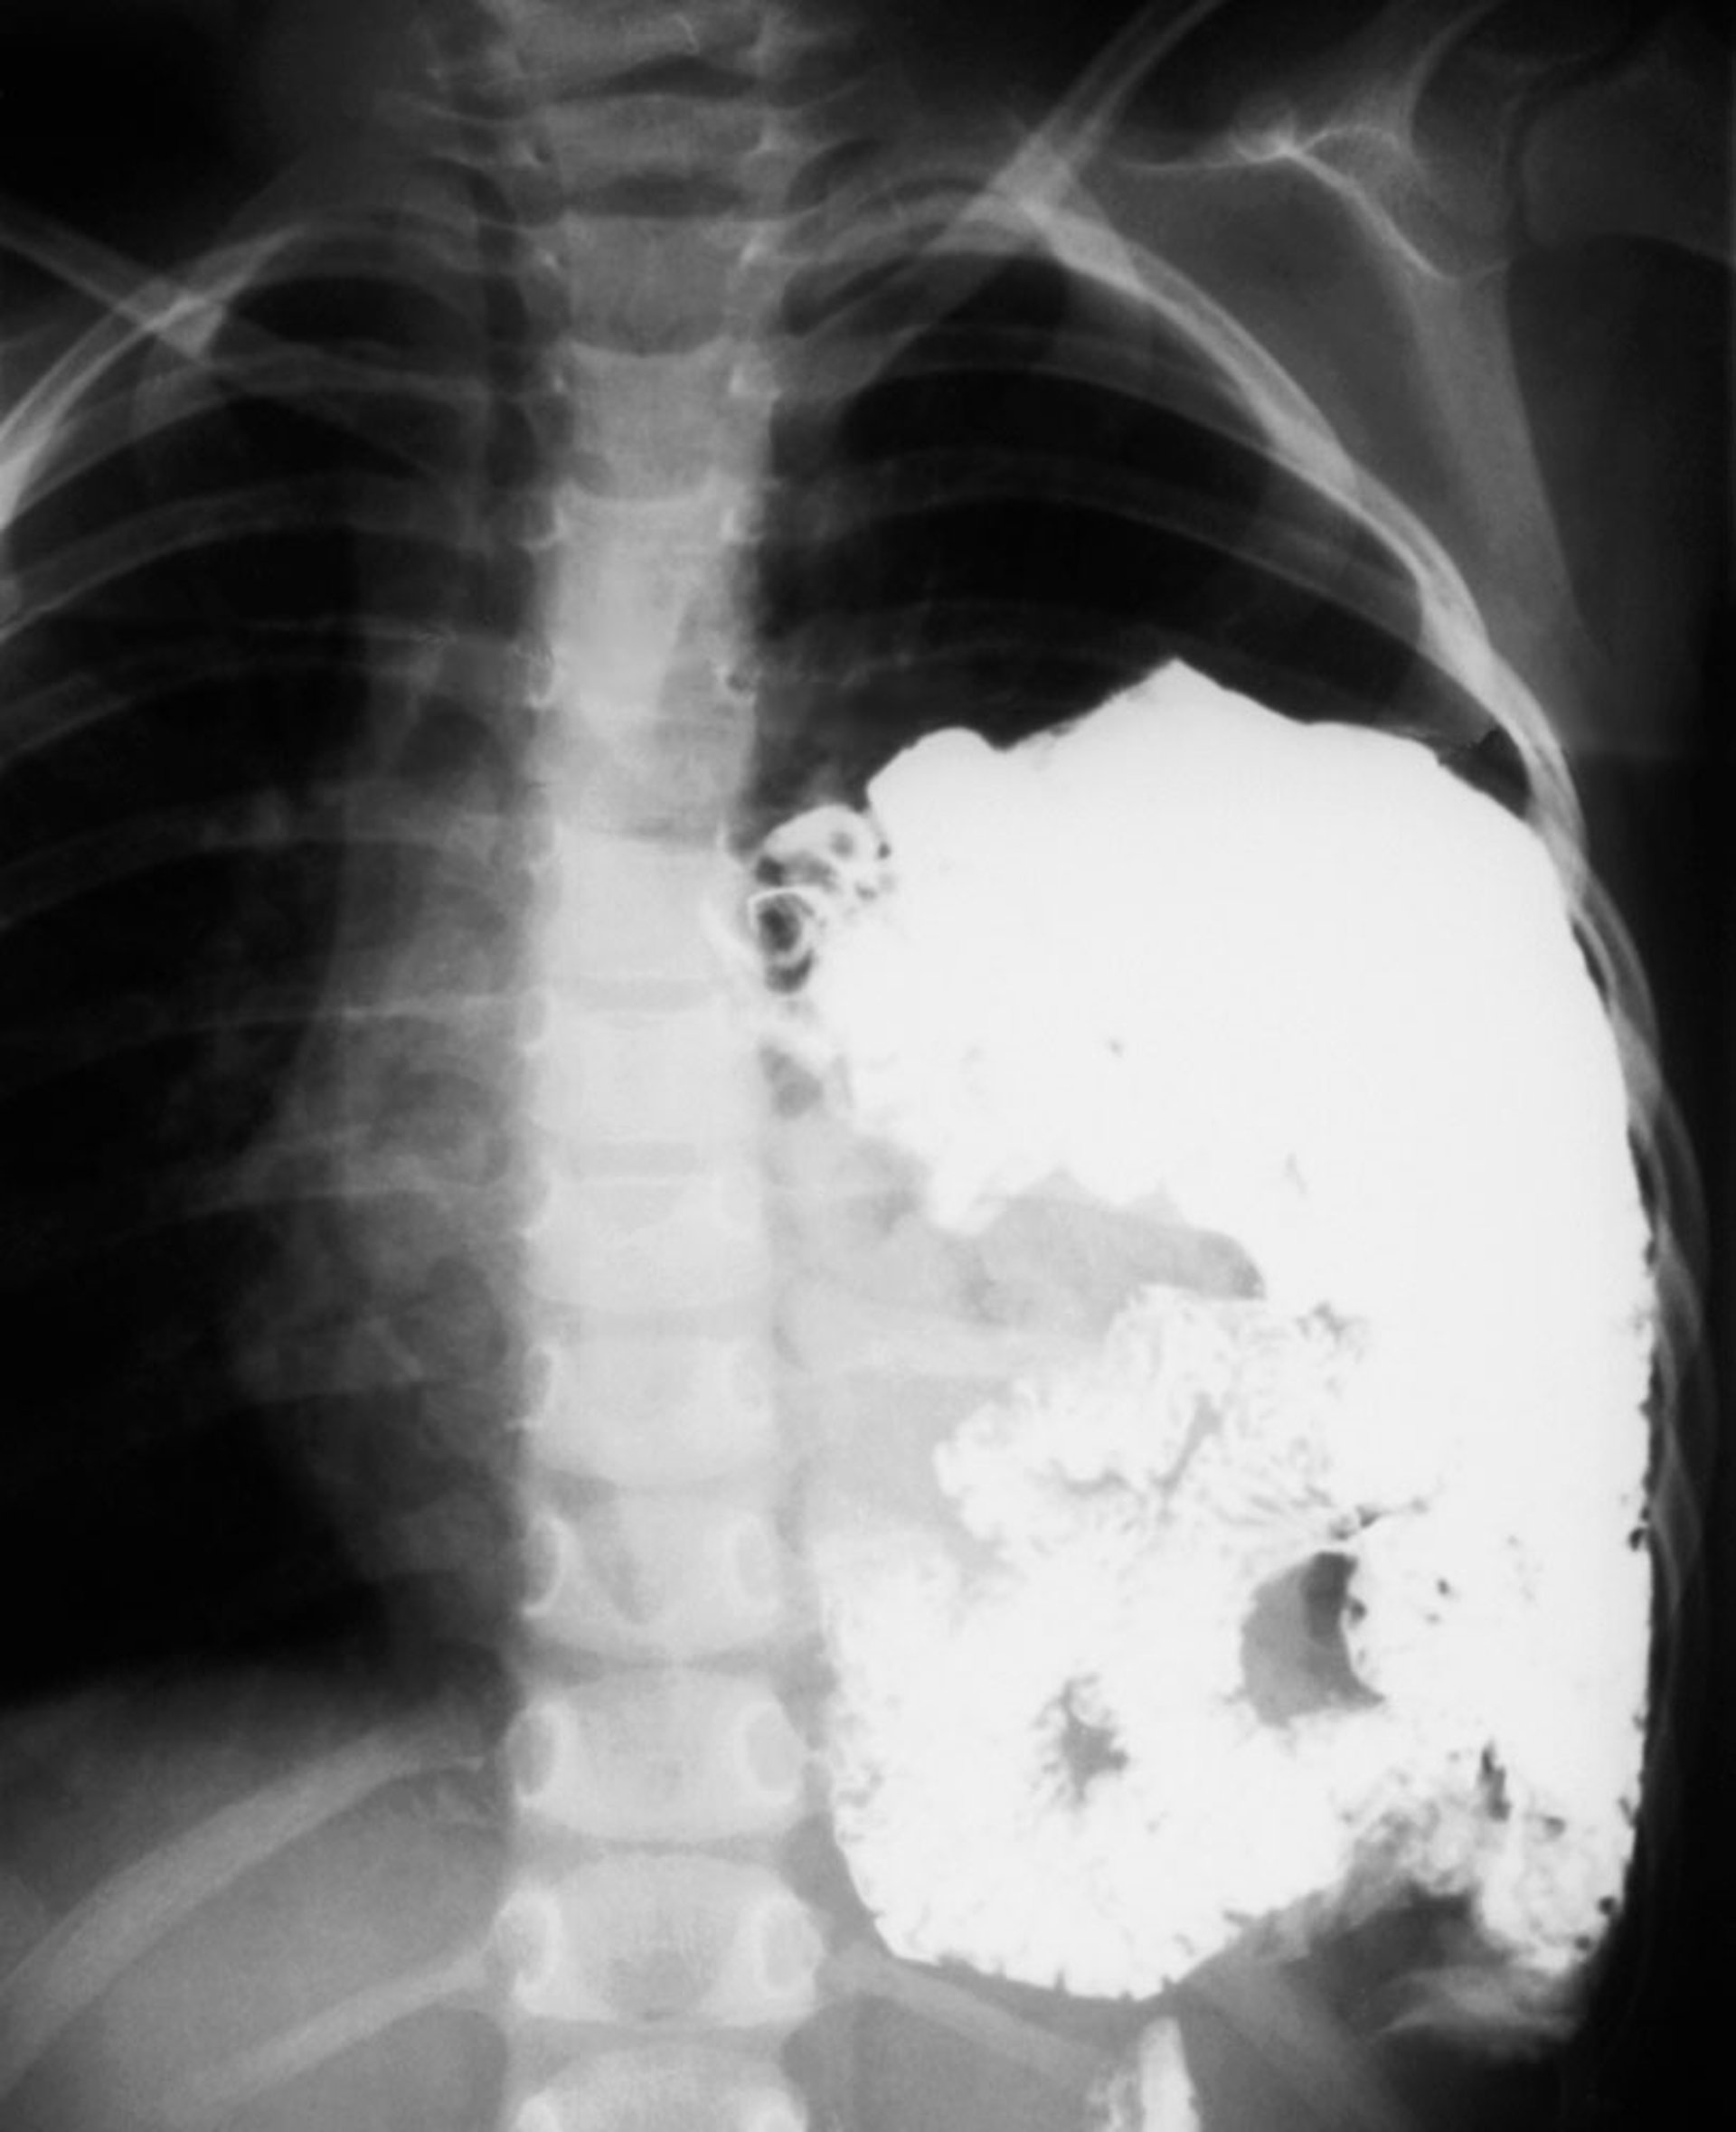

Après la naissance, le diagnostic repose sur la radiographie de thorax qui montre l'estomac et l'intestin herniés dans le thorax. En cas d'orifice large, on observe des anses intestinales remplies d'air dans l'hémithorax atteint et un déplacement controlatéral du cœur et des structures médiastinales. Si la radiographie est faite immédiatement après l'accouchement, avant que le nouveau-né n'ait avalé de l'air, le contenu abdominal peut n'apparaître que sous l'aspect d'une opacité sans air dans l'hémithorax.

Hernie diaphragmatique

Cette radiographie montre une hernie diaphragmatique congénitale chez un nouveau-né. Les intestins (spirales blanches) font saillie dans le thorax gauche (côté droit de la radiographie).

DU CANE MEDICAL IMAGING LTD/SCIENCE PHOTO LIBRARY